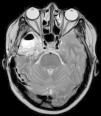

Para ello presentamos dos casos de pacientes mujeres de 50 y 42 años con crisis desde la infancia y diagnosticadas de esclerosis temporal mesial. Ambas fueron intervenidas por nosotros en el año 2000 mediante amigdalohipocampectomía con resección parcial amigdalar más lobectomía temporal izquierda y derecha respectivamente. Las dos pacientes no presentaron nuevas crisis parciales complejas durante los primeros 6 años, empeorando posteriormente por lo que fueron reintervenidas para monitorización con electrodos subdurales y profundos. En ambas se evidenció un inicio ictal compatible con el electrodo situado en la amígdala. La subsiguiente resección del tejido donde se situó el electrodo amigdalar dejó a las dos pacientes libres de crisis.

Two patients are presented who were 50 and 42 years old at the time of surgery. They suffered from seizures since childhood and were diagnosed with mesial temporal sclerosis. A temporal lobectomy with hippocampectomy and partial amygdalectomy was performed on both patients in the year 2000, with one patient operated on the right side and the other one on the left side. Both patients were seizure free after surgery for 6 years, but presented again with seizures after that time. They were evaluated again for surgery, and subdural grids were placed, together with a deep electrode in the remnants of the amygdala. The amygdalar electrode showed to be the seizure onset in the two cases, and its resection rendered both patients seizure free.